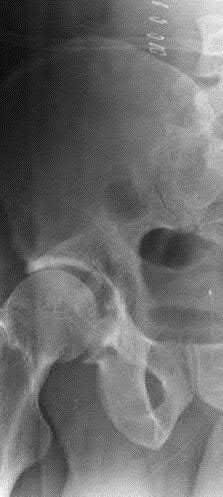

Figures A to C show radiographs of a 70 year-old male who fell on the ice 5 days ago. He could initially walk after the fall, but he is now unable to weight-bear on the leg due to pain. Physical examination shows diffuse ankle swelling, with no medial sided ankle tenderness. He is neurovascularly intact. The patient does not smoke and has no medical history. A gravity stress radiograph is demonstrated in Figure

D. After closed reduction, there is 2 mm of fracture displacement, no talar shift and the talocrural angle = 83 degrees. What is the most appropriate treatment?

Figure A demonstrates an AP radiograph of a Weber B fibula fracture with minimal medial clear space widening.

Figure B demonstrates a mortise radiograph of a Weber B fibula fracture with a congruent mortise.

Figure C demonstrates a lateral radiograph of a Weber B fibula fracture with a congruent mortise.

Figure D demonstrates a stress radiograph with minimal medial clear space widening.